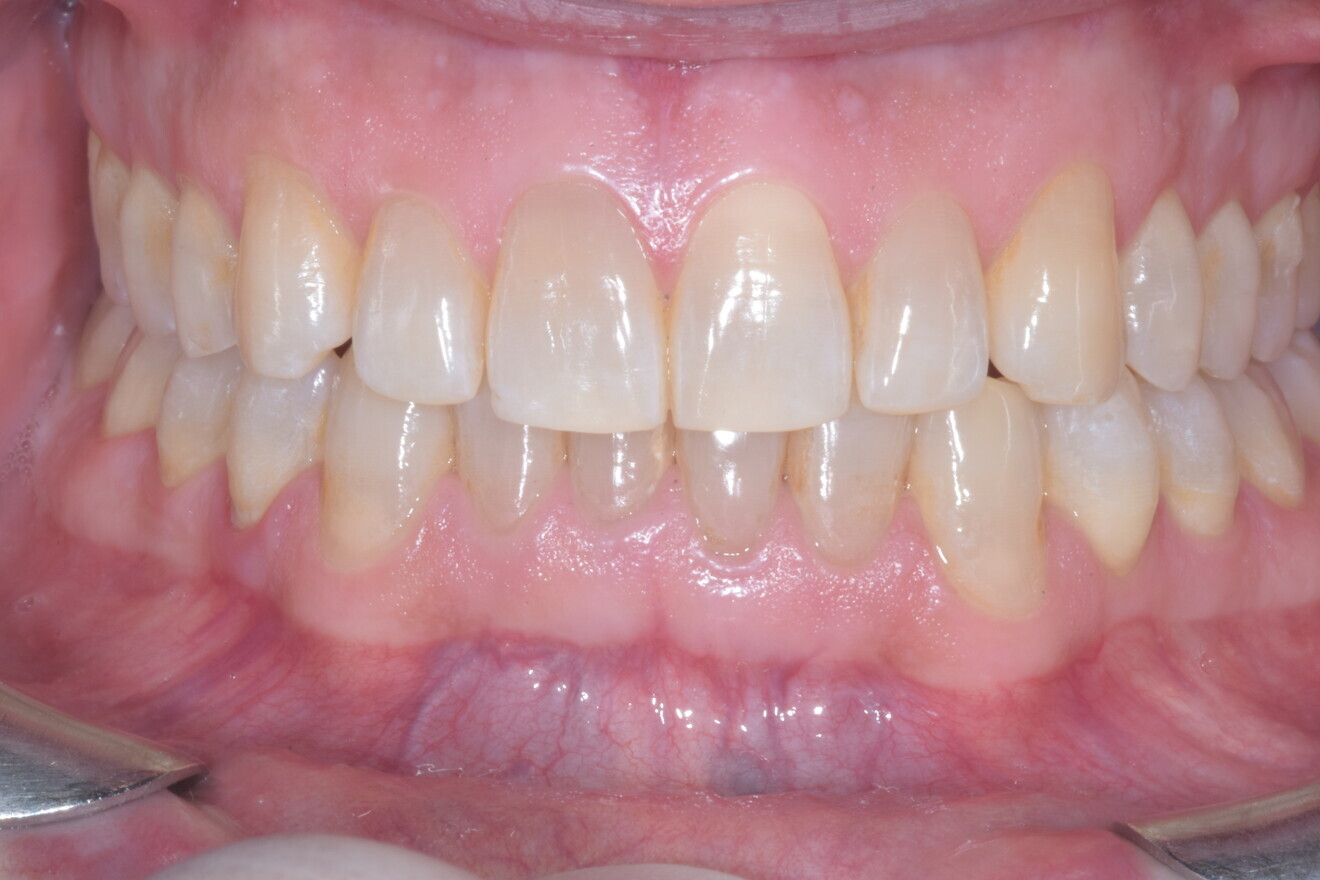

A 37-year-old male patient presented with the chief need for re establishing anterior alignment in both arches. Facial analysis showed a short face with a flat profile but proper chin projection (Figs. 9–12), and clinical examination revealed a skeletal Class I (ANB = 0.89°) and dental Class I malocclusion with severe deep bite (almost 100%), a deep curve of Spee, normal maxillary central incisor torque (Ui–FH = 110°), mild maxillary crowding and moderate mandibular crowding (Figs. 13–18). The deep bite components were represented in this patient by the severe skeletal condition of hypo divergent pattern (FMA = 14.24°) with normal maxillary and mandibular incisor inclination and decreased gonial angle (110.46°). Analysis of the cephalometric radiograph indicated a reduced lower anterior facial height, combined with a hypo-divergent pattern (Fig. 19). The only treatment option suggested was orthodontic treatment with aligners for deep bite correction with all the features described (bite ramps, pressure area, 3D curve of Spee levelling, Class II elastics and heavy occlusal contacts).

At the end of the treatment, Class I canine and molar relationships were obtained, maxillary incisor inclination was slightly increased (Ui–FH = 112°), mandibular incisor inclination (IMPA = 97.09°) was fully corrected by means of proclination and the divergency was slightly increased (SN–GoGn = 27°) because of the relative posterior extrusion and use of Class II elastics—a small variation (1°), which is interesting considering the age of the patient (Figs. 25–35). A balanced smile arc was obtained with an ideal relationship between the maxillary incisors and lower lip, and torque control of the lateral and posterior segments generated a broader smile.